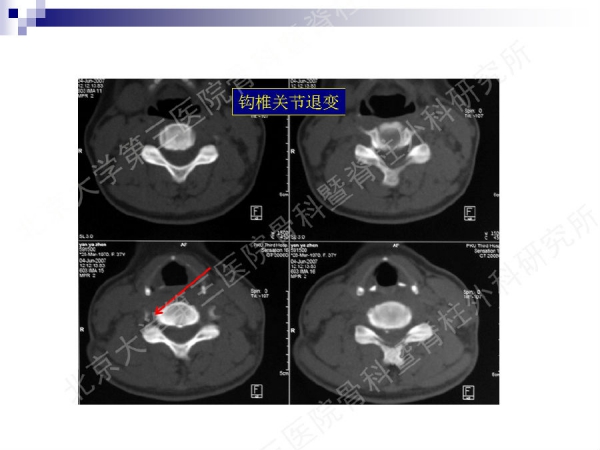

今天,在北京大学第三医院骨科暨脊柱外科研究所刘忠军教授分享的《颈椎人工椎间盘置换手术注意问题》课件中,他将通过大量影像资料、临床研究数据和长期随访结果,给大家介绍现阶段最重要的颈椎非融合技术——人工椎间盘置换术的适应证、禁忌证和其他需要密切注意的一些问题,提醒同道关注与手术技术及内植物相关的尺寸、终板顺列、中心轴线顺列等问题,严格把控手术指征,规范、精准地开展颈椎人工椎间盘置换手术,保障手术疗效。